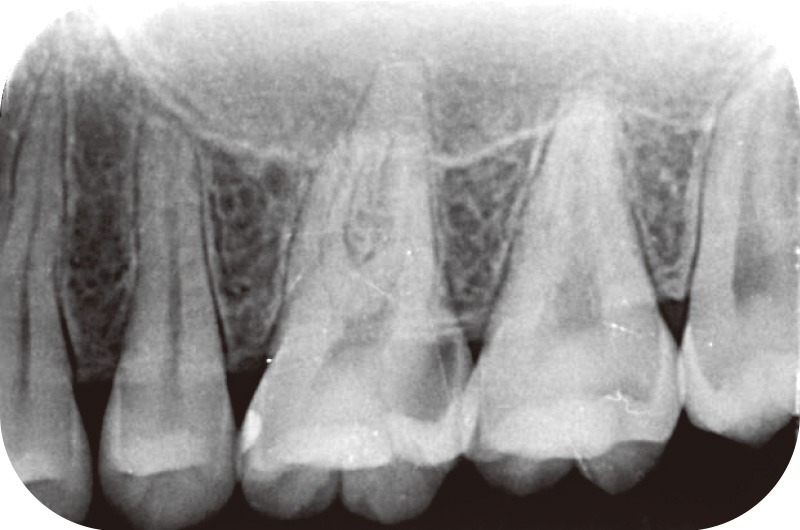

ついで通法通りに、「JIZAI」Ⅰ~Ⅲを用いて根管拡大(OTRモードm4 図8)を行い、初回処置を終了する。診療時間によっては初回処置を「JIZAI」ⅠやⅡに留めて、次回来院時に次のステップから始めるなど柔軟な対応が可能である。実際の症例では、処置後数回で疼痛の改善を認め、デンタルX線でも明らかな根尖病変は認められないため、根管充填を行い、感染根管治療を終了した(図9)。

![[写真] 根管充填後](/academic/dentalmagazine/wp-content/uploads/sites/2/2025/09/194-17_photo09.jpg)

図9 根管充填後。臨床症状は消失した。